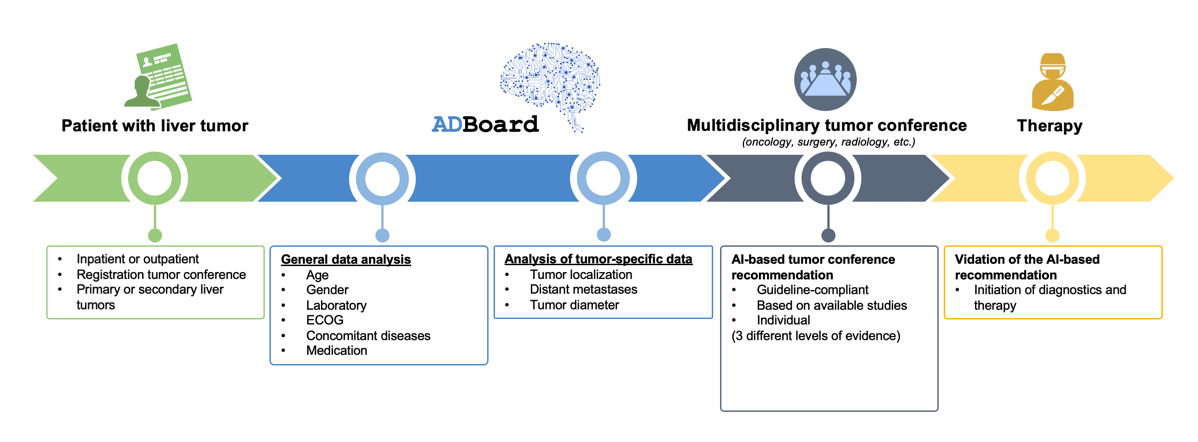

Interdisciplinary tumor conferences with physicians from different disciplines are the key to the best possible diagnosis and treatment of cancer. The information about the patients and the tumor that is necessary for the therapy decision is often not available to the treating physicians in full or in sufficient quality. This sometimes leads to a significant delay in the treatment of patients. Researchers in the ADBoard project want to contribute to further improving therapy decisions with the help of artificial intelligence (AI).

The aim of the project is to use a novel decision support system for liver tumors as a model. AI methods such as natural language processing and machine learning will provide the technical basis for automated data provision and decision support, including therapy recommendations. The robustness, reproducibility, transparency and explainability of the proposed therapy recommendations will be evaluated in a study. For this purpose, the therapy recommendations proposed by the system will be compared with the decisions of the tumor conferences actually conducted.

In the future, the therapy recommendations prepared using AI will support physicians in making timely and optimal therapy decisions for liver tumors. The long-term goal is to apply the new system in clinical practice and to transfer the system to other tumor types.